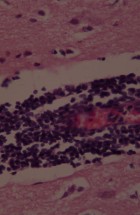

Делатност Одељења обухвата истраживачки и специјалистичко – стручни рад. Одељење се бави клиничком, патоанатомском, патохистолошком, имунохистохемијском и молекуларном дијагностиком обољења домаћих и дивљих животиња, као и патологијом репродукције. Рад на одељењу је организован кроз теренске и лабораторијске активности.

- Патохистолошка, цитолошка, имунохистохемијска и молекуларна дијагностика;